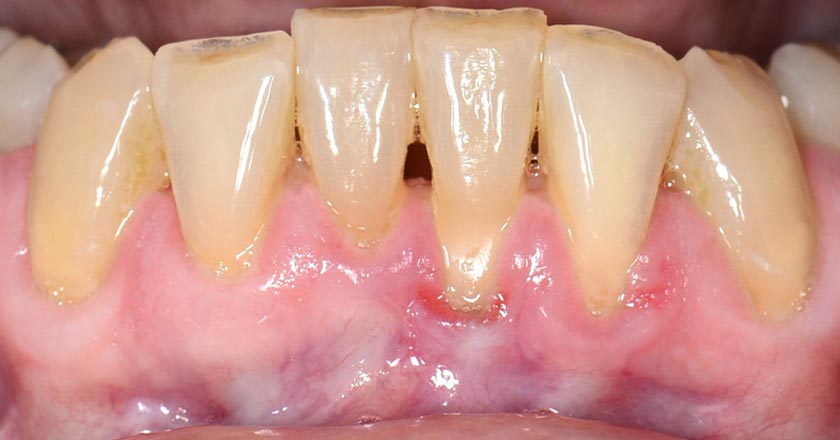

Gum Graft Lower - Before And After

Gum Graft Upper - Before And After